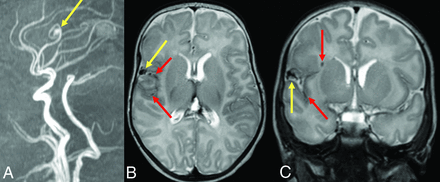

The findings of Engel et al discussed above can also be interpreted to support screening for brain VMs in children with HHT. Even if all 13 children with high-flow brain VMs and HHT had been diagnosed with HHT before brain VM clinical presentation, almost one-half would have presented with hemorrhagic stroke in the absence of screening,25 a number that the authors deem unacceptably high. Figure 2 shows images from a child with HHT who presented with a life-threatening cerebellar hemorrhage due to a brain AVM. The AVM could have been successfully treated before the hemorrhage occurred if it had been detected on screening. Figure 3 shows images from a 2-month-old infant whose pial AVF was identified on screening and who underwent successful embolization at 6 months of age when surveillance imaging demonstrated progression. The embolization was without complications and resulted in obliteration of the AVF. Findings of repeat imaging performed 7.5 years after treatment were stable without AVF recurrence. The child is neurologically and cognitively healthy at 9 years of age. Figure 4 shows MR imaging and subsequent DSA from a girl with ENG-related HHT. The DSA demonstrated the subtle finding on MR imaging in greater detail and identified a second small AVM that was not visible on MR imaging.

A 13-year-old boy with HHT who presented with severe headache and altered mental status. A, Coronal noncontrast head CT shows an acute left cerebellar hemisphere hemorrhage and intraventricular hemorrhage in the bilateral lateral ventricles and fourth ventricle. Anterior-posterior (B) and lateral (C) views on digital DSA depict a left cerebellar AVM with arterial supply from the left anterior and posterior inferior cerebellar arteries, left superior cerebellar artery, and deep venous drainage through the transverse sinus.

An infant diagnosed with HHT due to a familial ENG variant who had screening MR imaging of the brain and MRA of the head at 2 months of life had a pial AVF with hemosiderin deposition. Sagittal reformat (A) TOF-MRA demonstrates the right fontal AVF (yellow arrow). Axial (B) and coronal (C) T2-weighted MR images confirm the location of the AVF (yellow arrows) as well as adjacent hemosiderin deposition (red arrows) suggestive of prior hemorrhage.